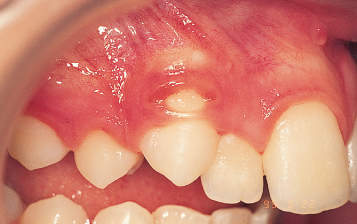

دندان نهفته چیست؟

دندان نهفته به دندانی گفته میشود که در زمان مناسب از لثه خارج نشده و بهطور کامل داخل...